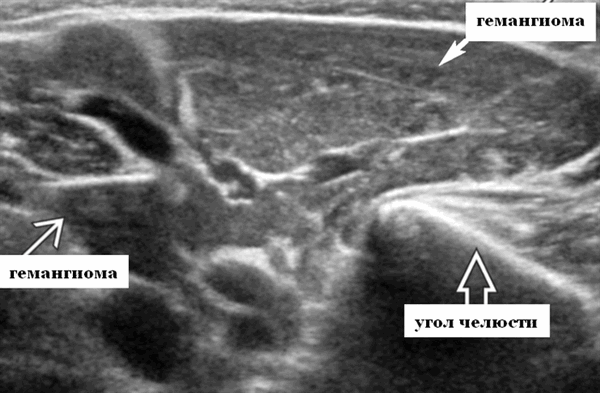

Визуализация при ультразвуковом сканировании. Общие характеристики

Лучшая диагностическая подсказка. Четко выраженная опухоль с диффузной гиперваскуляризацией внутри очага поражения / интенсивным усилением кровотока на УЗИ с ЦДК. Сосуды внутри и рядом с образованием во время фазы пролиферации (ФП). Уменьшение размера за счет замещения жировой ткани во время фазы инволюции (ФИ)

Результаты ультразвукового исследования слюнных желез

Серошкальное УЗИ. Четко выраженная солидная некальцинированная опухоль мягких тканей. Однородная картина эхоструктуры. ПФ: Гипоэхогенный вид по сравнению с паренхимой околоушной железы; ИФ: эхоструктура от изо- до умеренно гиперэхогенной